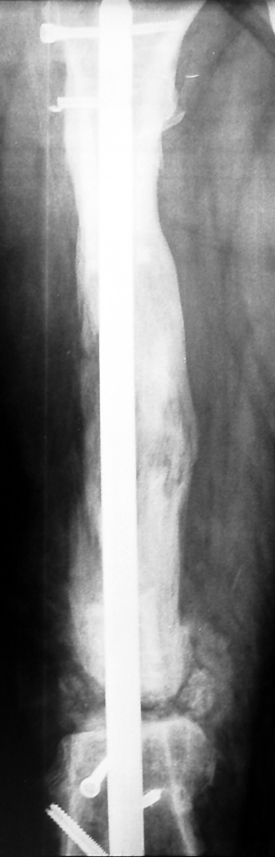

Uygun radikal debridman tüm nekrotik kemik ve yumuşak dokuların çıkartılmasını gerektirir, ve sıklıkla uzuvda instabiliteye neden olur. Kalan kemik ve yumuşak doku defektinin bir şekilde fiksasyonu ve rekonstrüksiyonu gereklidir. İlizarov’un ortaya koyduğu distraksiyon osteogenezi yöntemi, kaynamanın elde edilmesi, deformitenin düzeltilmesi, bacak boy eşitsizliğinin giderilmesi ve segmental defektlerin rekonstrükte edilmesi için başarıyla kullanılmaktadır.

Eksternal fiksatör ile geçen süre (eksternal fiksasyon indeksi), gereken distraksiyon miktarına bağlıdır ve bu süre boyunca bazı komplikasyonlarla karşılaşılabilir. Distraksiyon dönemi sona erdikten sonra, distraksiyon süresinin iki katını aşan konsolidasyon döneminde hastalar eksternal fiksatörü zorlukla tolere edebilirler. Yeterli konsolidasyon sağlanmadan eksternal fiksatör çıkartılırsa ise kırıklar, deformite ve kısalık oluşabilir. Hastanın fiksatör ile birlikte geçirdiği sürenin azaltılması ve böylece hasta konforunun ve aktivite düzeyinin arttırılması için intramedüller çivi üzerinden uzatma yöntemi uygulanmaktadır. Bu yöntemde distraksiyon dönemi sona erdiğinde kemiğin içindeki çivi statik olarak kilitlenmekte ve eksternal fiksatör çıkartılmaktadır. Stabilizasyon intramedüller çivi tarafından sağlandıktan sonra konsolidasyon dönemi gerçekleşmektedir. Bu şekilde hem eksternal fiksatörün uzun süre kalmasından hem de erken çıkartılmasından kaynaklanan komplikasyonların önüne geçilmektedir.

Vaka 3